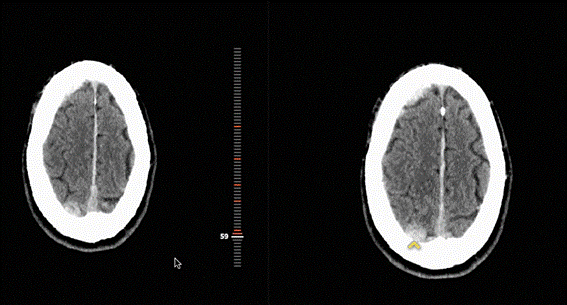

Na FIDI, o processo funciona da seguinte maneira: após a realização de um exame, as imagens são enviadas para o servidor, que anonimiza estas imagens e as envia para processamento por IA na nuvem. Ela analisa as imagens, marca eventuais lesões e devolve para o médico, onde os exames são reidentificados e enviados para a central de laudos. Na central de laudos, exames graves são automaticamente priorizados, permitindo ao , agilizando o atendimento.

Trabalhamos em parceria com a CARPL, e suporte da Philips, para implementar IA nos exames de imagem, especialmente radiografias de tórax. O objetivo é oferecer suporte rápido e preciso para a equipe clínica e para os pacientes. Atualmente, em um pronto socorro, é comum que laudos radiológicos levem algumas horas para ficarem prontos devido à grande quantidade de exames realizados, mas com o uso da IA, podemos entregá-lo em poucos minutos.